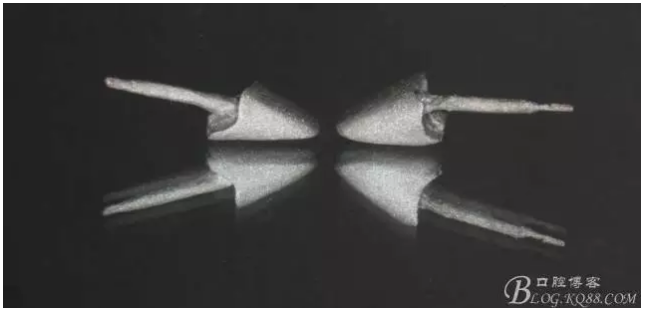

缺損太多 是必須用金屬樁修復(fù)的,

還要有足夠的牙本質(zhì)肩領(lǐng),大家現(xiàn)在可以看到患者的下頜套筒冠還是非常好的